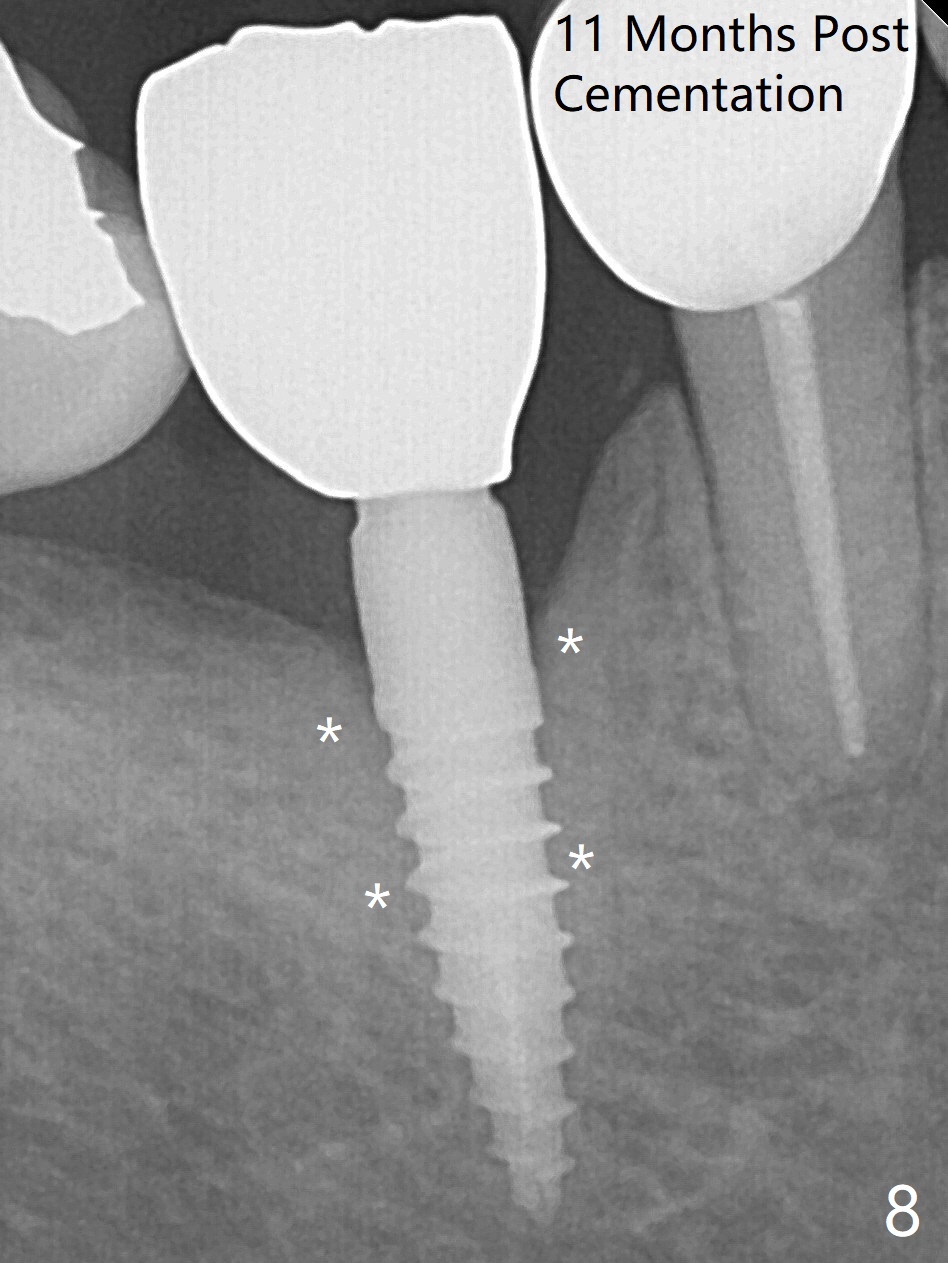

Incision reveals a narrow ridge and a narrow mesiodistal space at #30 (Fig.1).  It seems that a 1-piece implant is indicated.  Due to limited mouth opening, a 1.2 mm drill is unstable in place after use for 10 mm; instead a 1.5 mm drill is able to be inserted for 8 mm (Fig.2).  A 3x10(2) mm 1-piece dummy implant is placed with 40 Ncm at an apparently acceptable level (Fig.3 >).  Clinically a few threads are exposed buccally.  When a definitive implant with the same dimension is inserted with 45 Ncm, it looks seated too deep (Fig.4,5).  The latter is noted after suturing.  The implant is backed up for a few turns so that the length of the abutment appears a little more reasonable.  Introspectively, a 4 mm cuff should have been used after ridge reduction.  Although there is no bone loss 4 months postop (Fig.6), the abutment margin (Fig.7 arrow) is subgingival (red dashed line: gingival margin).  Diode laser is used for gingivectomy prior to impression.  The bone density around the implant increases 11 months post cementation (Fig.8 *), probably related to recurrent #18 infection.  The patient uses floss after meal.